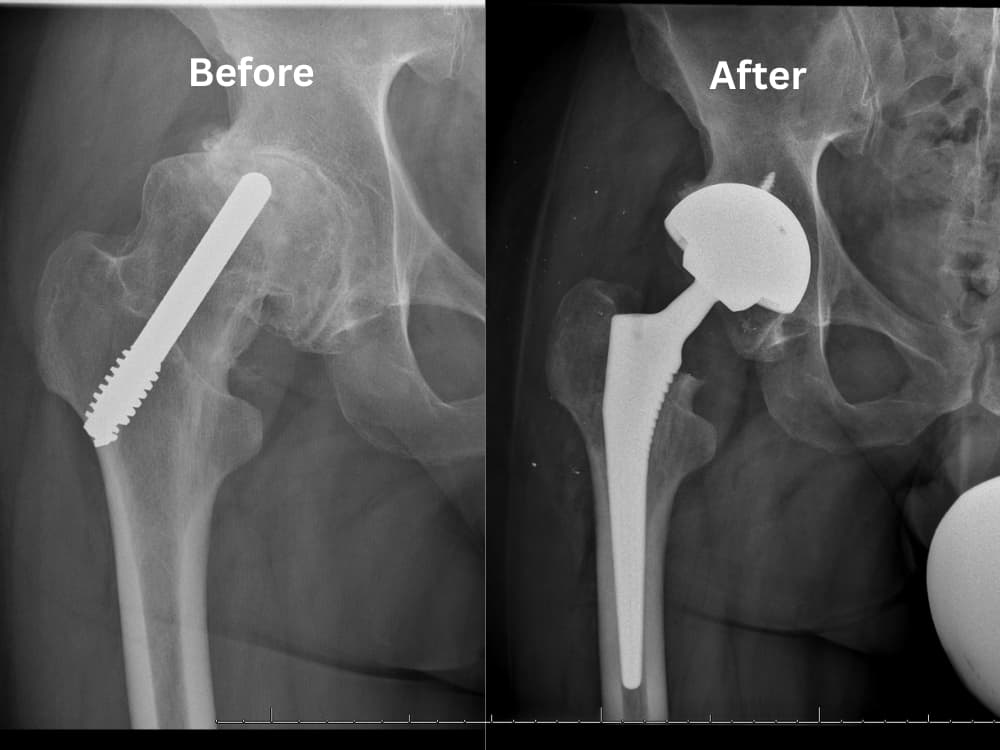

Minimally invasive hip replacement is a modern surgical approach focused on replacing only the damaged hip joint surfaces while preserving healthy surrounding tissues. The procedure is performed through a small incision of approximately 8–12 cm (3–5 inches), significantly minimizing muscle disruption and promoting faster recovery. Refined and advanced by Dr. Samih Tarabichi over many years of clinical expertise, the technique avoids cutting major muscles and tendons, maintaining the hip’s natural biomechanics. The damaged hip joint surfaces are carefully removed and replaced with a new joint constructed from advanced titanium and medical-grade ceramic materials, along with the insertion of an artificial cartilage layer. This highly durable joint design is engineered to provide superior longevity, often lasting longer than conventional artificial hip implants while delivering smooth, pain-free movement. The incision is then closed using specialized techniques designed to support rapid healing and early mobility. This innovative method ensures accuracy, long-term durability, and quicker return to normal activities, setting a new standard in modern hip arthroplasty

- Prepare the joint: The damaged cartilage and worn surfaces of the hip joint are carefully removed from the femoral head (ball) and the acetabulum (socket), along with a minimal amount of underlying bone.

- Position the implants: The removed bone and cartilage are replaced with advanced titanium and medical-grade ceramic components that recreate the natural ball-and-socket structure of the hip joint. These components are either securely press-fit or fixed with medical cement for long-term stability.

- Insert the liner (artificial cartilage): A durable medical-grade liner is placed between the new joint components to ensure smooth, pain-free movement and reduce friction, restoring normal hip function.